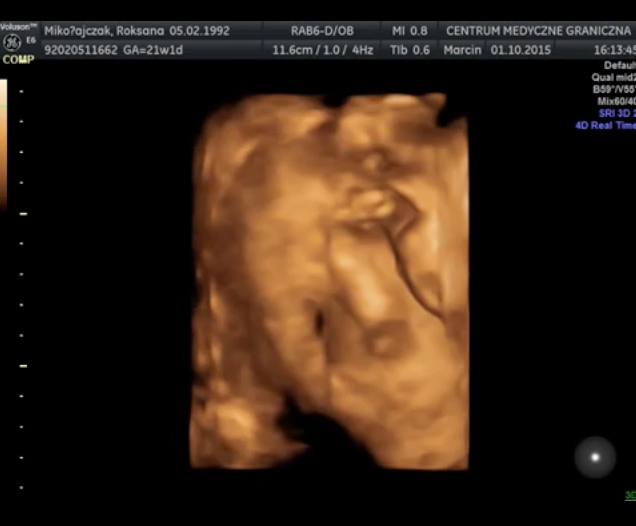

Wyniki badań prenatalnych są bardzo dobre. Obecnie trwa 23 tydzień ciąży, a mała waży 500 gram. Lekarz zalecił mi jednak kontrolę przepływu krwi, ponieważ obecne wyniki mieszczą się w górnej granicy normy 101cm/s. Wykonanie USG nie było wcale takie proste – maleńka Kasia jest bardzo ruchliwa i nie pozwalała się zmierzyć podczas badania. W czasie jego trwania udało się nagrać kilka krótkich filmów i zdjęć, możecie je zobaczyć poniżej. Kolejne badanie prenatalne odbędzie się 10-go grudnia. Termin porodu wyznaczono na 11 lutego i prawdopodobnie odbędzie się za pomocą cesarskiego cięcia.